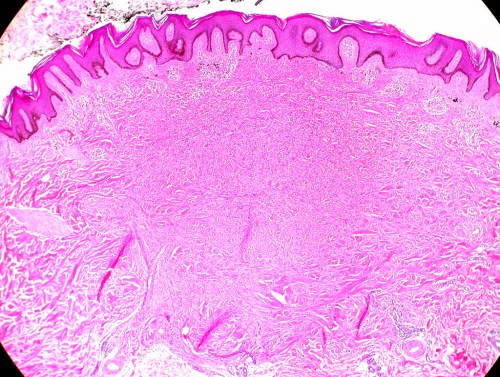

Imagen histológica del dermatofibroma

Imagen histológica del dermatofibroma. Foto: eutham

Al microscopio se aprecia que es un tumor de la dermis, simétrico y separado de la epidermis suprayacente por una zona libre de tumor (zona Grenz).

Está formado por células alargadas parecidas a fibroblastos, histiocitos espumosos, células gigantes multinucleadas y algún linfocito. El tejido que lo sustenta es muy laxo (mixoide).

Las variantes histológicas son numerosas y de ahí los distintos nombres con que se conoce a este tumor.